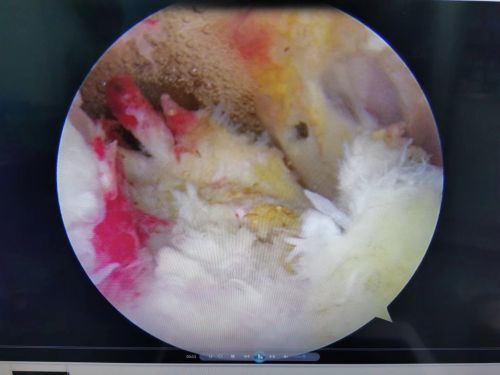

王靖教授团队为患者施行肩关节镜下肩袖缝合手术。

肩关节镜下可以看到肩袖肌腱全层撕裂伴回缩。

入院后完善相关检查,核磁共振证实了之前的判断,患者右侧冈上肌肌腱和肩胛下肌肌腱全层断裂并回缩,这种情况是不可能自己长好的,除了会出现肩部反复疼痛以外,肩部力量也会逐渐下降,只能手术修复。王靖主任为患者制定了手术方案,并于9月11日带领团队为患者施行全麻下右肩关节镜检查、肩袖缝合手术。